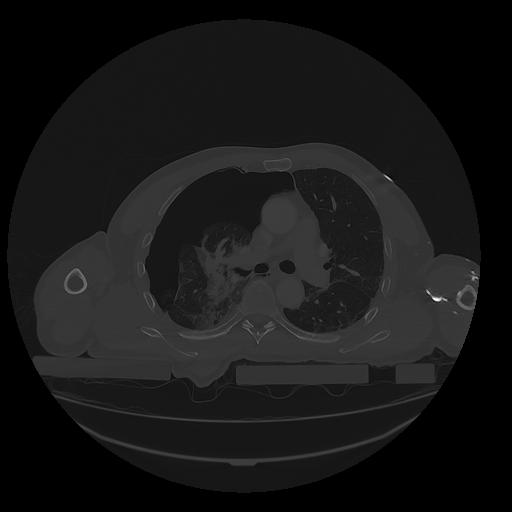

31 PULMON,CE,Vol,1.0,PULMON,,